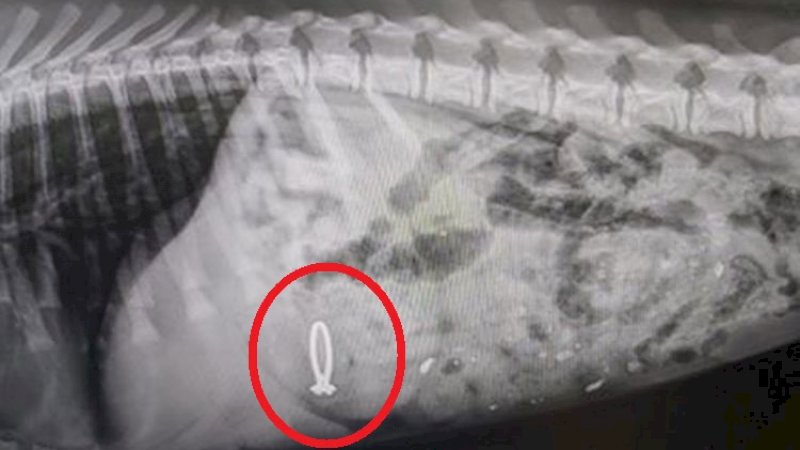

Anjing itu bernama Pepper. Hasil foto rontgen menunjukkan cincin berada di perut anjing.

Rumah sakit hewan kemudian melanjutkan untuk membagikan hasil rontgen cincin yang terlihat di dalam perut Pepper.